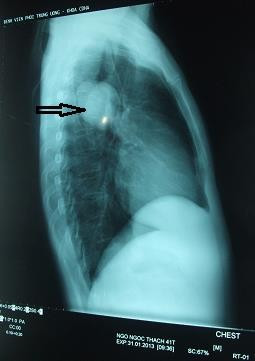

Chụp hình ảnh bệnh nhân bị sán chó làm tổ tạo u trong phổi.

“Bệnh nhân được chẩn đoán u phổi và bị chỉ định cắt bỏ một thùy phổi kèm khối u. Khối u của bệnh nhân là một bọc nước. Tuy nhiên, chúng tôi vô cùng kinh hãi khi trong bọc nước là hàng nghìn đầu sán đang ngoe nguẩy. Kết quả xét nghiệm khẳng định là loại sán dây chó”, tiến sĩ Đề nói.

Bệnh nhân nhập viện Lao phổi Trung ương để điều trị, kết quả chụp X-quang cho thấy bệnh nhân có 4 khối u khổng lồ trên phổi.